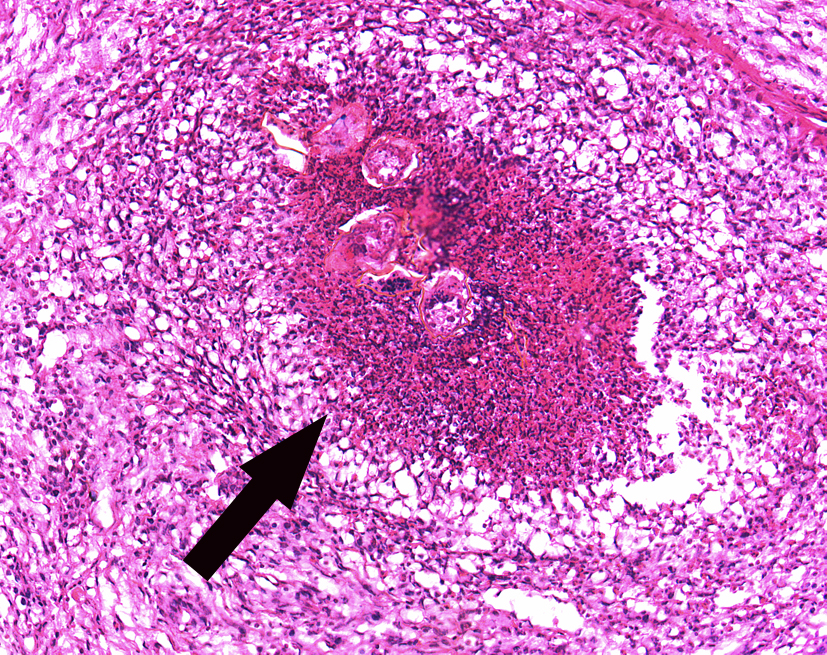

3.Experimental acute schistosomiasis of the liver (rabbit)